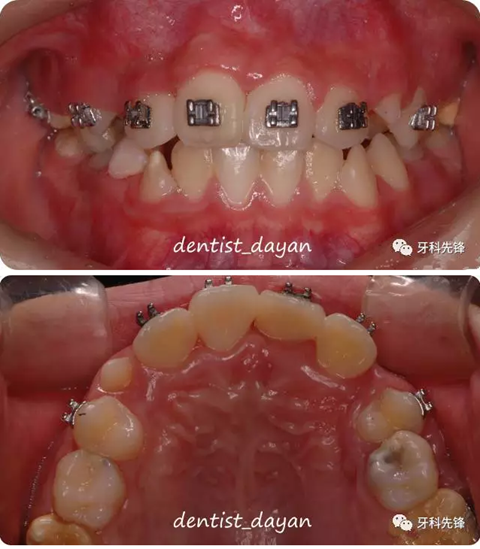

1個月后,待11可以粘接托槽時,粘接托槽,上鎳鈦絲將11繼續(xù)向HE方牽引。。

2個月后,牙齒牽引到位,雖然轉(zhuǎn)矩有點不太理想,決定待整體矯正時解決。

保持三個月后,拆除托槽。。。

這個病例中,多生牙對拔除是個比較難的地方。。。多生牙擁擠在一起,又要避免碰到正常牙,操作確實是不易的,正畸治療中未對11的轉(zhuǎn)矩加以改正,這也是比較遺憾的地方。。